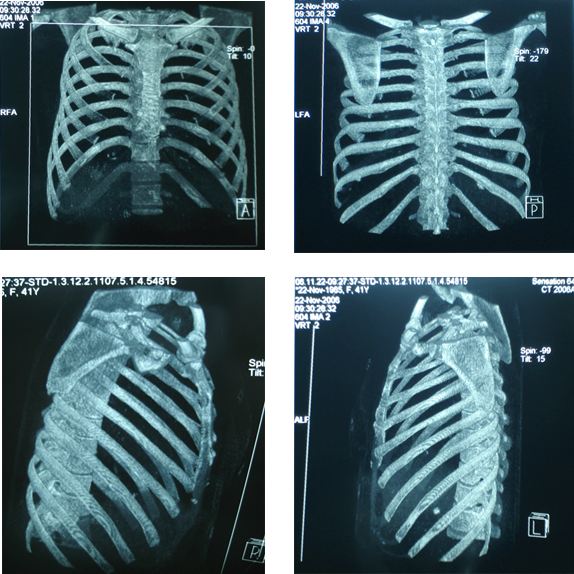

Năm 2006 bệnh nhân đến BV Bạch Mai khám định kỳ được làm các xét nghiệm siêu âm ổ bụng, chụp CT ngực 64 dãy, CT ổ bụng… nhưng không phát hiện thấy bất thường. Chất chỉ điểm khối u trong giới hạn bình thường.

Hình ảnh chụp CT 64 dãy, không phát hiện thấy tổn thương (CT-)

BN được chỉ định làm xạ hình xương toàn thân để kiểm tra tổng thể toàn bộ hệ thống xương, phát hiện ổ di căn xương sườn số 4 trái.

Ung thư đại tràng di căn xương

CT (-), Xạ hình xương với SPECT, Tc 99m- MDP (+)

Bàn luận: Trong điều trị ung thư việc xác định đúng giai đoạn bệnh có ý nghĩa quyết định phương pháp điều trị, từ đó mang lại hiệu quả điều trị tốt nhất cho người bệnh. Nếu chỉ dùng các phương pháp chẩn đoán thông thường rất dễ bỏ sót tổn thương qua đó đánh giá không đúng giai đoạn bệnh. Sự ra đời của các máy SPECT, PET, SPECT/CT, PET/CT ghi hình ở mức độ tế bào, mức độ phân tử, theo nguyên tắc chuyển hoá khi chưa có sự thay đổi về giải phẫu thực sự,  là bước tiến quan trọng trong việc phân loại đúng, sớm giai đoạn bệnh cũng như việc điều trị ung thư. ở BN này, bằng các kỹ thuật chẩn đoán thông thường  (ngay cả với CT 64 dãy đầu dò) đều cho kết quả hoàn toàn bình thường, nhưng khi dùng kỹ thuật xạ hình bằng máy SPECT đã phát hiện ổ di căn xương trên xạ hình xương thì thái độ điều trị đã hoàn toàn thay đổi. BN được tiếp tục điều trị hoá chất và chống huỷ xương, hiện tại bệnh nhân khoẻ mạnh, bệnh ổn định.